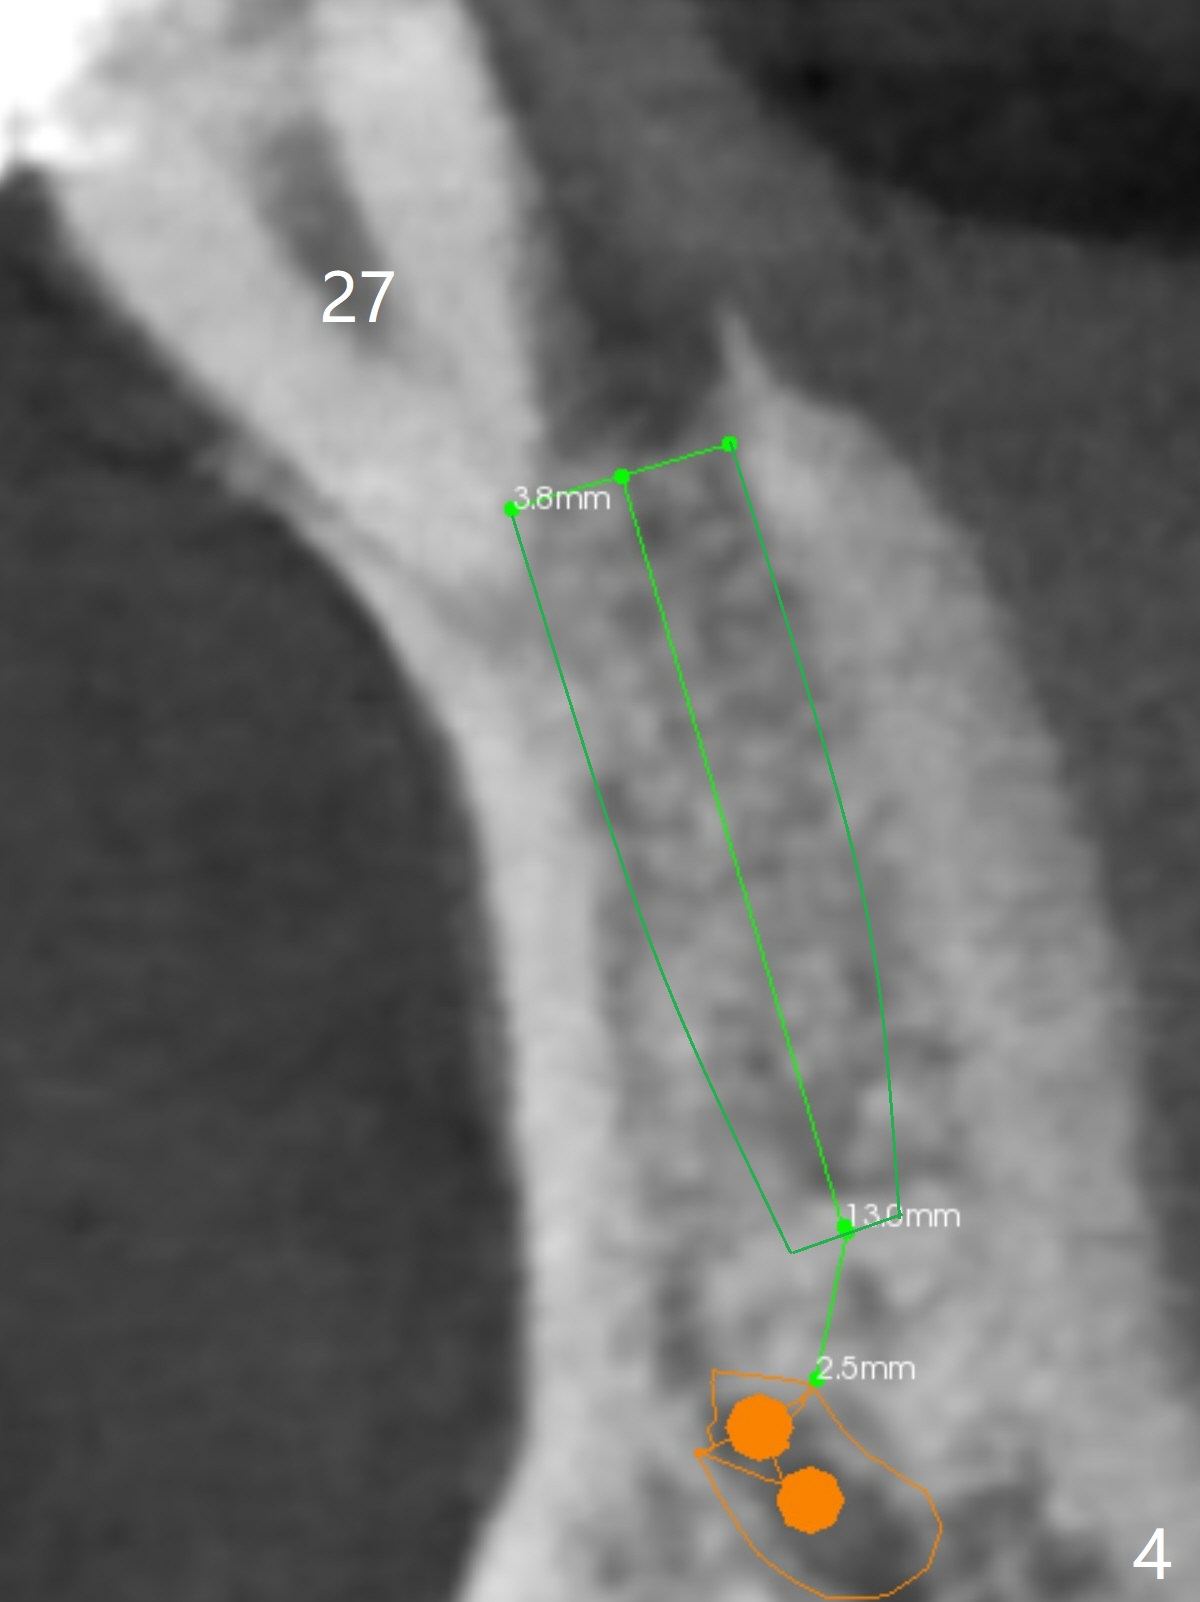

A 46-year-old man has finished upper implant placement (9-11 15 UR provisional) and wants to have lower anterior done (Long Cuff Wax up 2). The tooth #28 has exfoliated, while #22-27 FPD has mobility. It appears that the anchor tooth #22 has more severe periodontitis than that of #27. If the condition remains the same, section FPD between #22 and 23. Implants will be placed probably at #23, 26, 27 and 28. If both of the anchor teeth are non-salvageable, the possible implant will be at #22, one incisor, 27 and 28. In fact the patient requests an implant at #28.